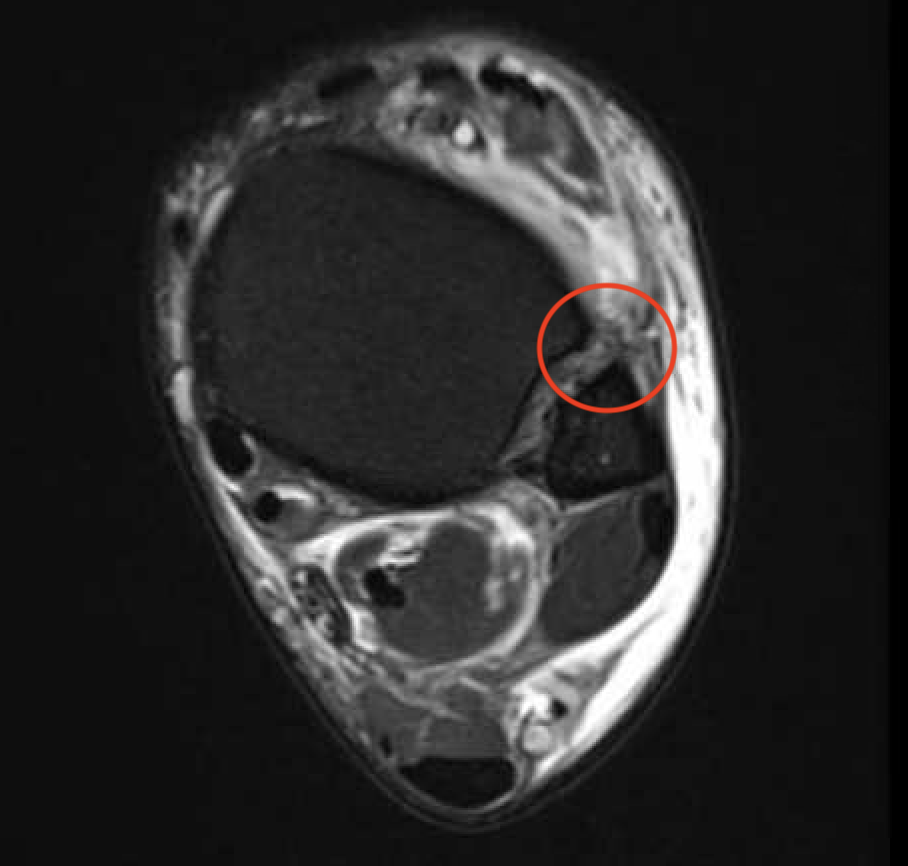

MRI

Tear of AITFL / intact PITFL

Tear of AITFL, intact PITFL, and syndesmotic injury with external rotation of the fibula

Tear of AITFL & PITFL with syndesmotic widening